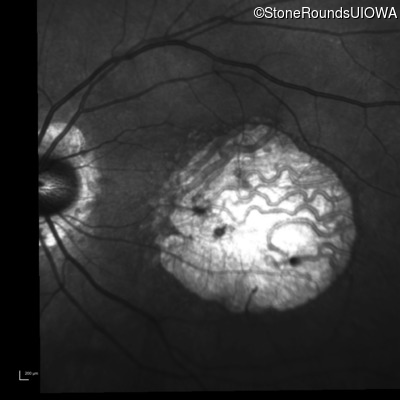

Infrared Fundus Photograph - Right - 20/50 -1

Exemplar